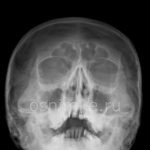

Для определения внешнего вида гайморита на рентгенограмме необходимо осознать, что воспалительные изменения и накопившаяся жидкость проявляются светлыми областями на темном фоне изображения.

При нормальном состоянии придаточные пазухи на рентгеновском снимке не содержат воздуха. На изображении здорового человека они выглядят как темные области по обе стороны от носа и имеют полуовальную форму. Для определения того, является ли область синуса нормальной или патологической, ее оттенок сравнивают с оттенком глазницы. В норме цвет синусов и глазниц совпадает на рентгеновском снимке.

Уже в университетах обучают определять гайморит на рентгеновском снимке (см. фото 5). Здоровые носовые пазухи изображены темными полуовальными образованиями. Гайморит на снимке представлен затемнением в верхних горизонтальных уровнях. По снимку можно отчетливо увидеть тень с волнистым контуром – жидкость такого типа: гнойная, слизистая, катаральная.

Гайморит на рентгене

Почти всегда при гайморите на рентгене (фото 6) обнаруживается характерное изображение, напоминающее молоко в стакане: в черных пазухах видно белое инфильтративное содержимое. Рентгеновский снимок пазух носа при гайморите, в сочетании с диагностическими симптомами, помогает врачу поставить правильный диагноз. Однако при скоплении гноя при гайморите (фото внизу страницы), патологические тени округлой формы не наблюдаются.